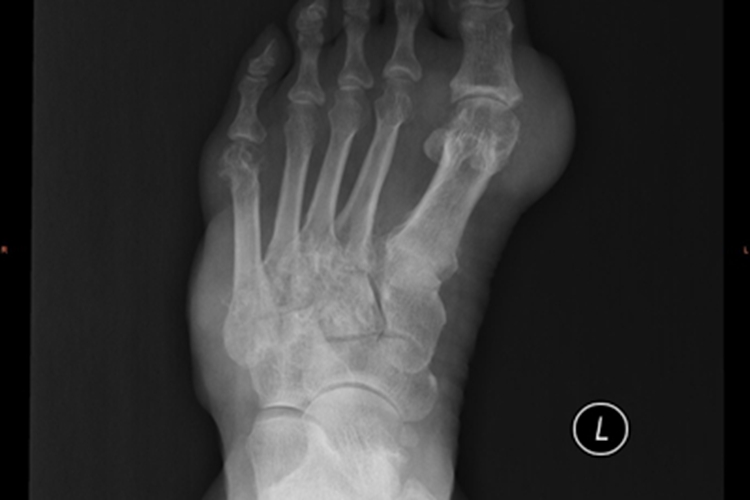

痛风未规范治疗可导致左脚的关节处有痛风石积累,有多处向外隆起,变形严重,其影像学图像可显示多个关节处均有白色团块状阴影附着。